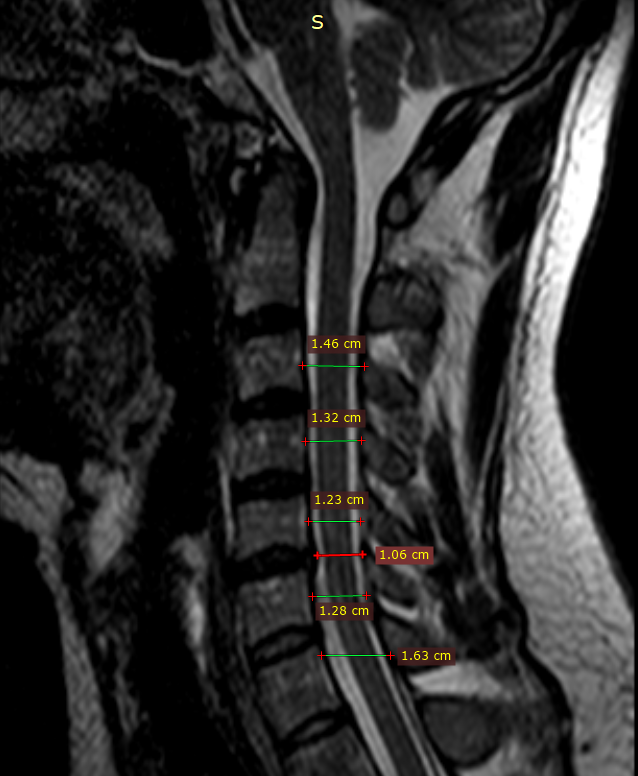

ШОП.

Получено изображение сегментов С1-Th1. Дистрофические изменения 1-2 стадии во всех

исследованных сегментах, в виде полосовидной дегидратации м/п дисков и снижения

дифференцировки фиброзного кольца и пульпозного ядра.

Шейный лордоз сглажен. Сколиотической деформации позвоночника

Не определяется.

Взаимоотношения в переднем и боковых атланто-аксиальных, а также атланто-затылочных суставах правильные. Костно-деструктивных изменений не определяется. Линия заднего контура ровная.

Краниовертебральный переход без особенностей.

Асимметрия позвоночных артерий D>S, гипоплазия левой позвоночной артерии в сегменте V2. Мелкие центральные протрузии в сегментах С3-С5, сагиттальным размером до 1,5 мм, с лёгким дискодуральным конфликтом.

Протрузия на широком основании в сегменте С5-С6 с латерализацией вправо, сагиттальным размером до 2 мм с дискомедуллярным конфликтом 1 степени.

Мелкая центральная протрузия в сегменте С6-С7, с лёгким дискодуральным конфликтом.

Признаков миелопатии не получено. Канал спинного мозга не расширен.

Исходный сагиттальный размер позвоночного канала на уровне С4-С7 не более 13 мм.

Паравертебральные мягкие ткани не изменены. Данных за t-r spinalis не получено. Новообразований не определяется. Минимальный субхондральный отек тел позвонков в сегменте С5-С6 (изменения по типу Модик I), без выпота под продольными связками.

Заключение:

Остеохондроз шейного отдела позвоночника 1-2 стадий. Врожденный, относительно узкий позвоночный канал. Мелкие центральные протрузии в сегментах С3-С5. Протрузия на широком основании в сегменте С5-С6 с латерализацией вправо. Мелкая центральная протрузия в сегменте С6-С7. Реактивные изменения в сегменте С5-С6. Асимметрия позвоночных артерий D>S, гипоплазия левой позвоночной артерии в сегменте V2. Рекомендована консультация невролога.